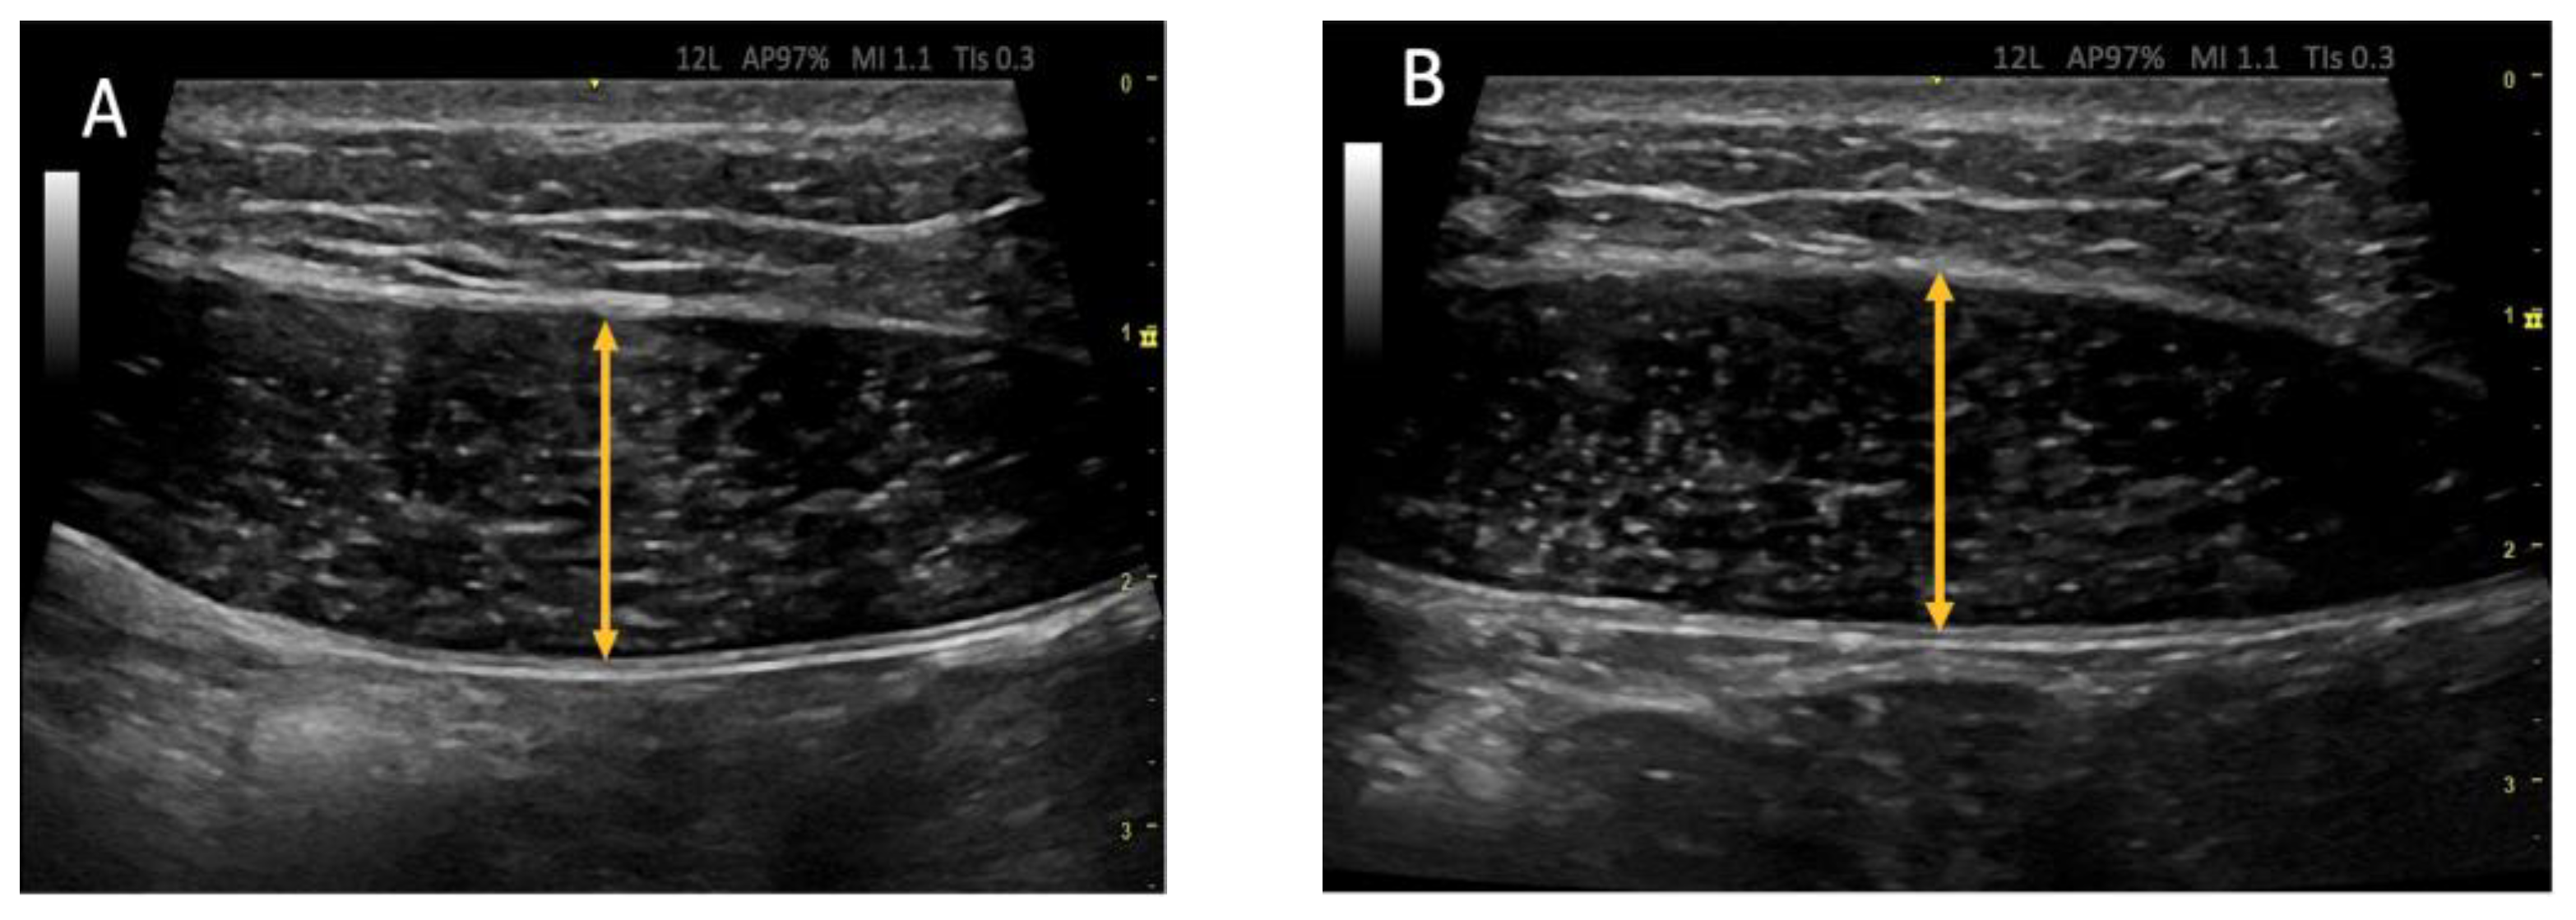

2.7. Ultrasound Protocol

2.8. Outcome Measurements/Descriptive Data